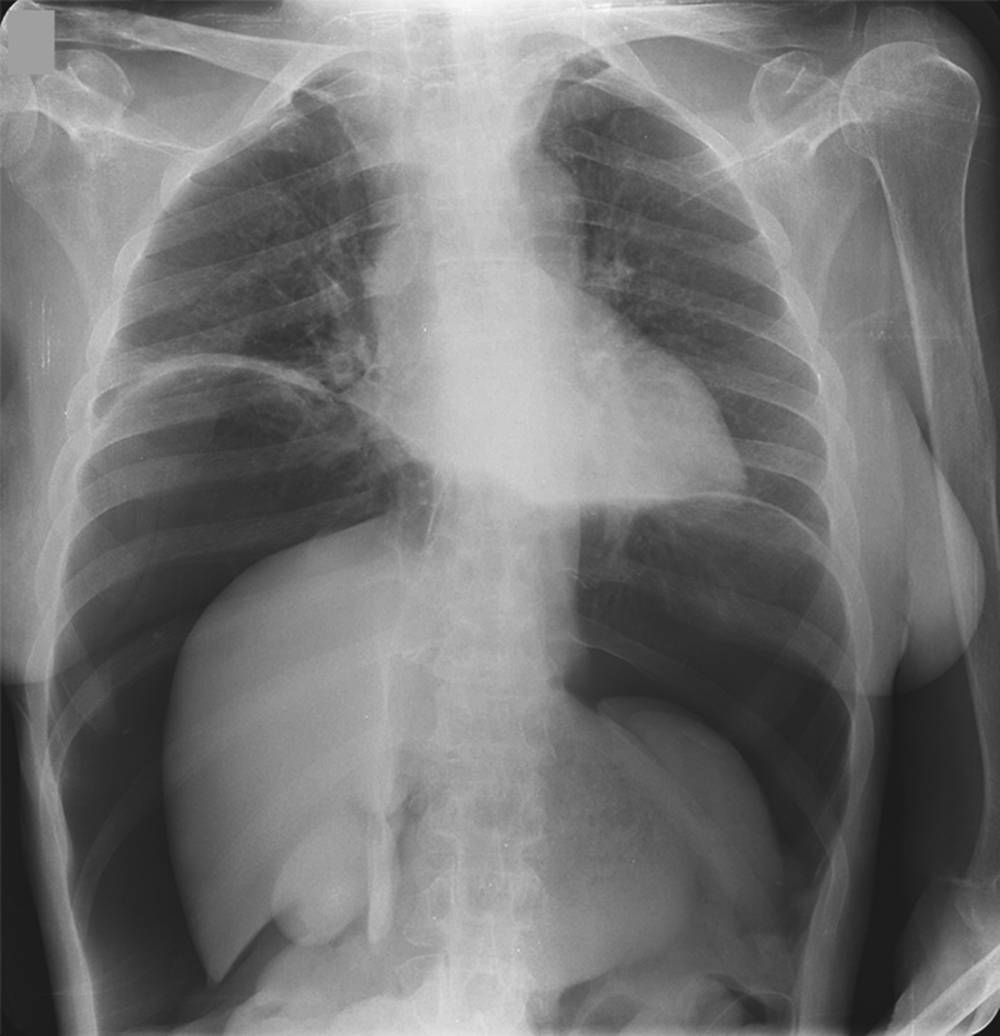

A 69-year-old woman presented to the emergency department with a 3-day history of progressively worsening abdominal distention and pain. She was taking dexamethasone for cerebral edema associated with glioblastoma multiforme.